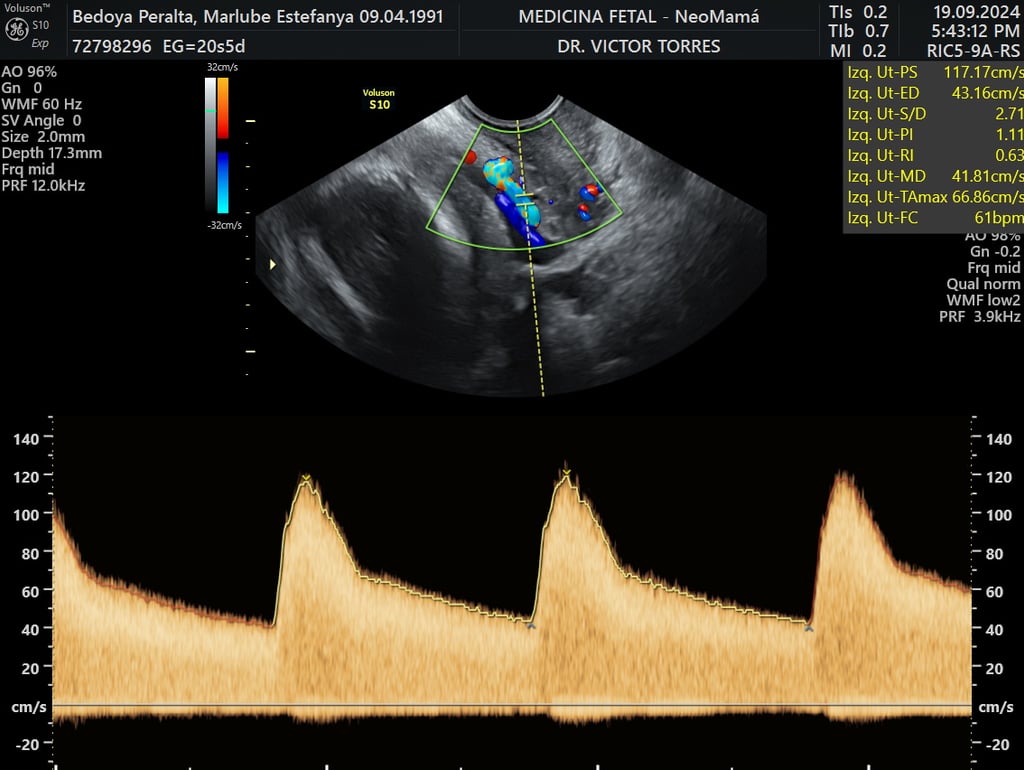

ecografía de crecimiento Doppler

24 - 40 semanas